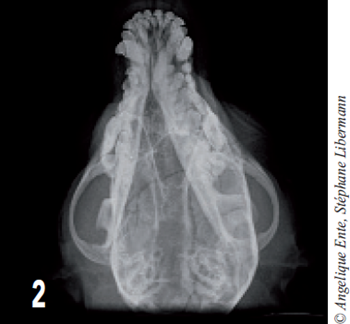

On effectue ensuite des radiographies de face et de profil du crâne (figures 1 et 2) : ces dernières montrent une fracture de l’os frontal induisant une embarrure.

D’autres traits de fractures sont visibles latéralement et caudalement (jusqu’à l’occiput).

Figure 2 – Radiographie de crâne en décubitus ventral. Les traits de fracture s’étendent jusqu’à l’occiput et l’os temporal gauche.